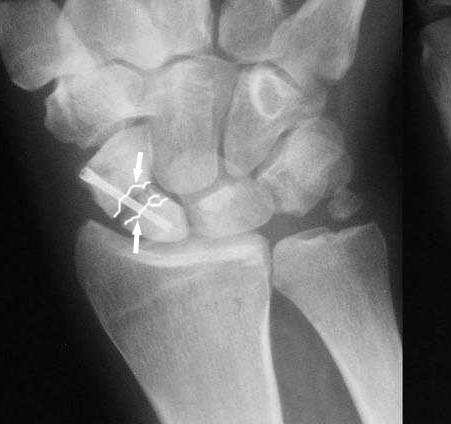

Ув. Данил! По моему мнению все-таки ложный сустав -склероз отломков (приложение), 5 мес, диастаз. Для подтверждения можно выполнить КТ кистевого сустава (формирование замыкательной пластинки, склероз концов отломков и т.д.,), а так же по КТ можно выявить сохраняется ли подвывих каких-либо костей запястья или нет. При наличии ложного сустава целесообразно будет удалить винт,обработать концы отломков, разрушив замыкательные пластинки и  выполнить остеосинтез ладьевидной кости винтом с костной аутопластикой зоны псевдоартроза (либо гидроксиаппатитом...) Гипс 1,5 мес мин. Снимков найти сейчас не получилось. позже дошлю.

Имя     : 1016.jpg